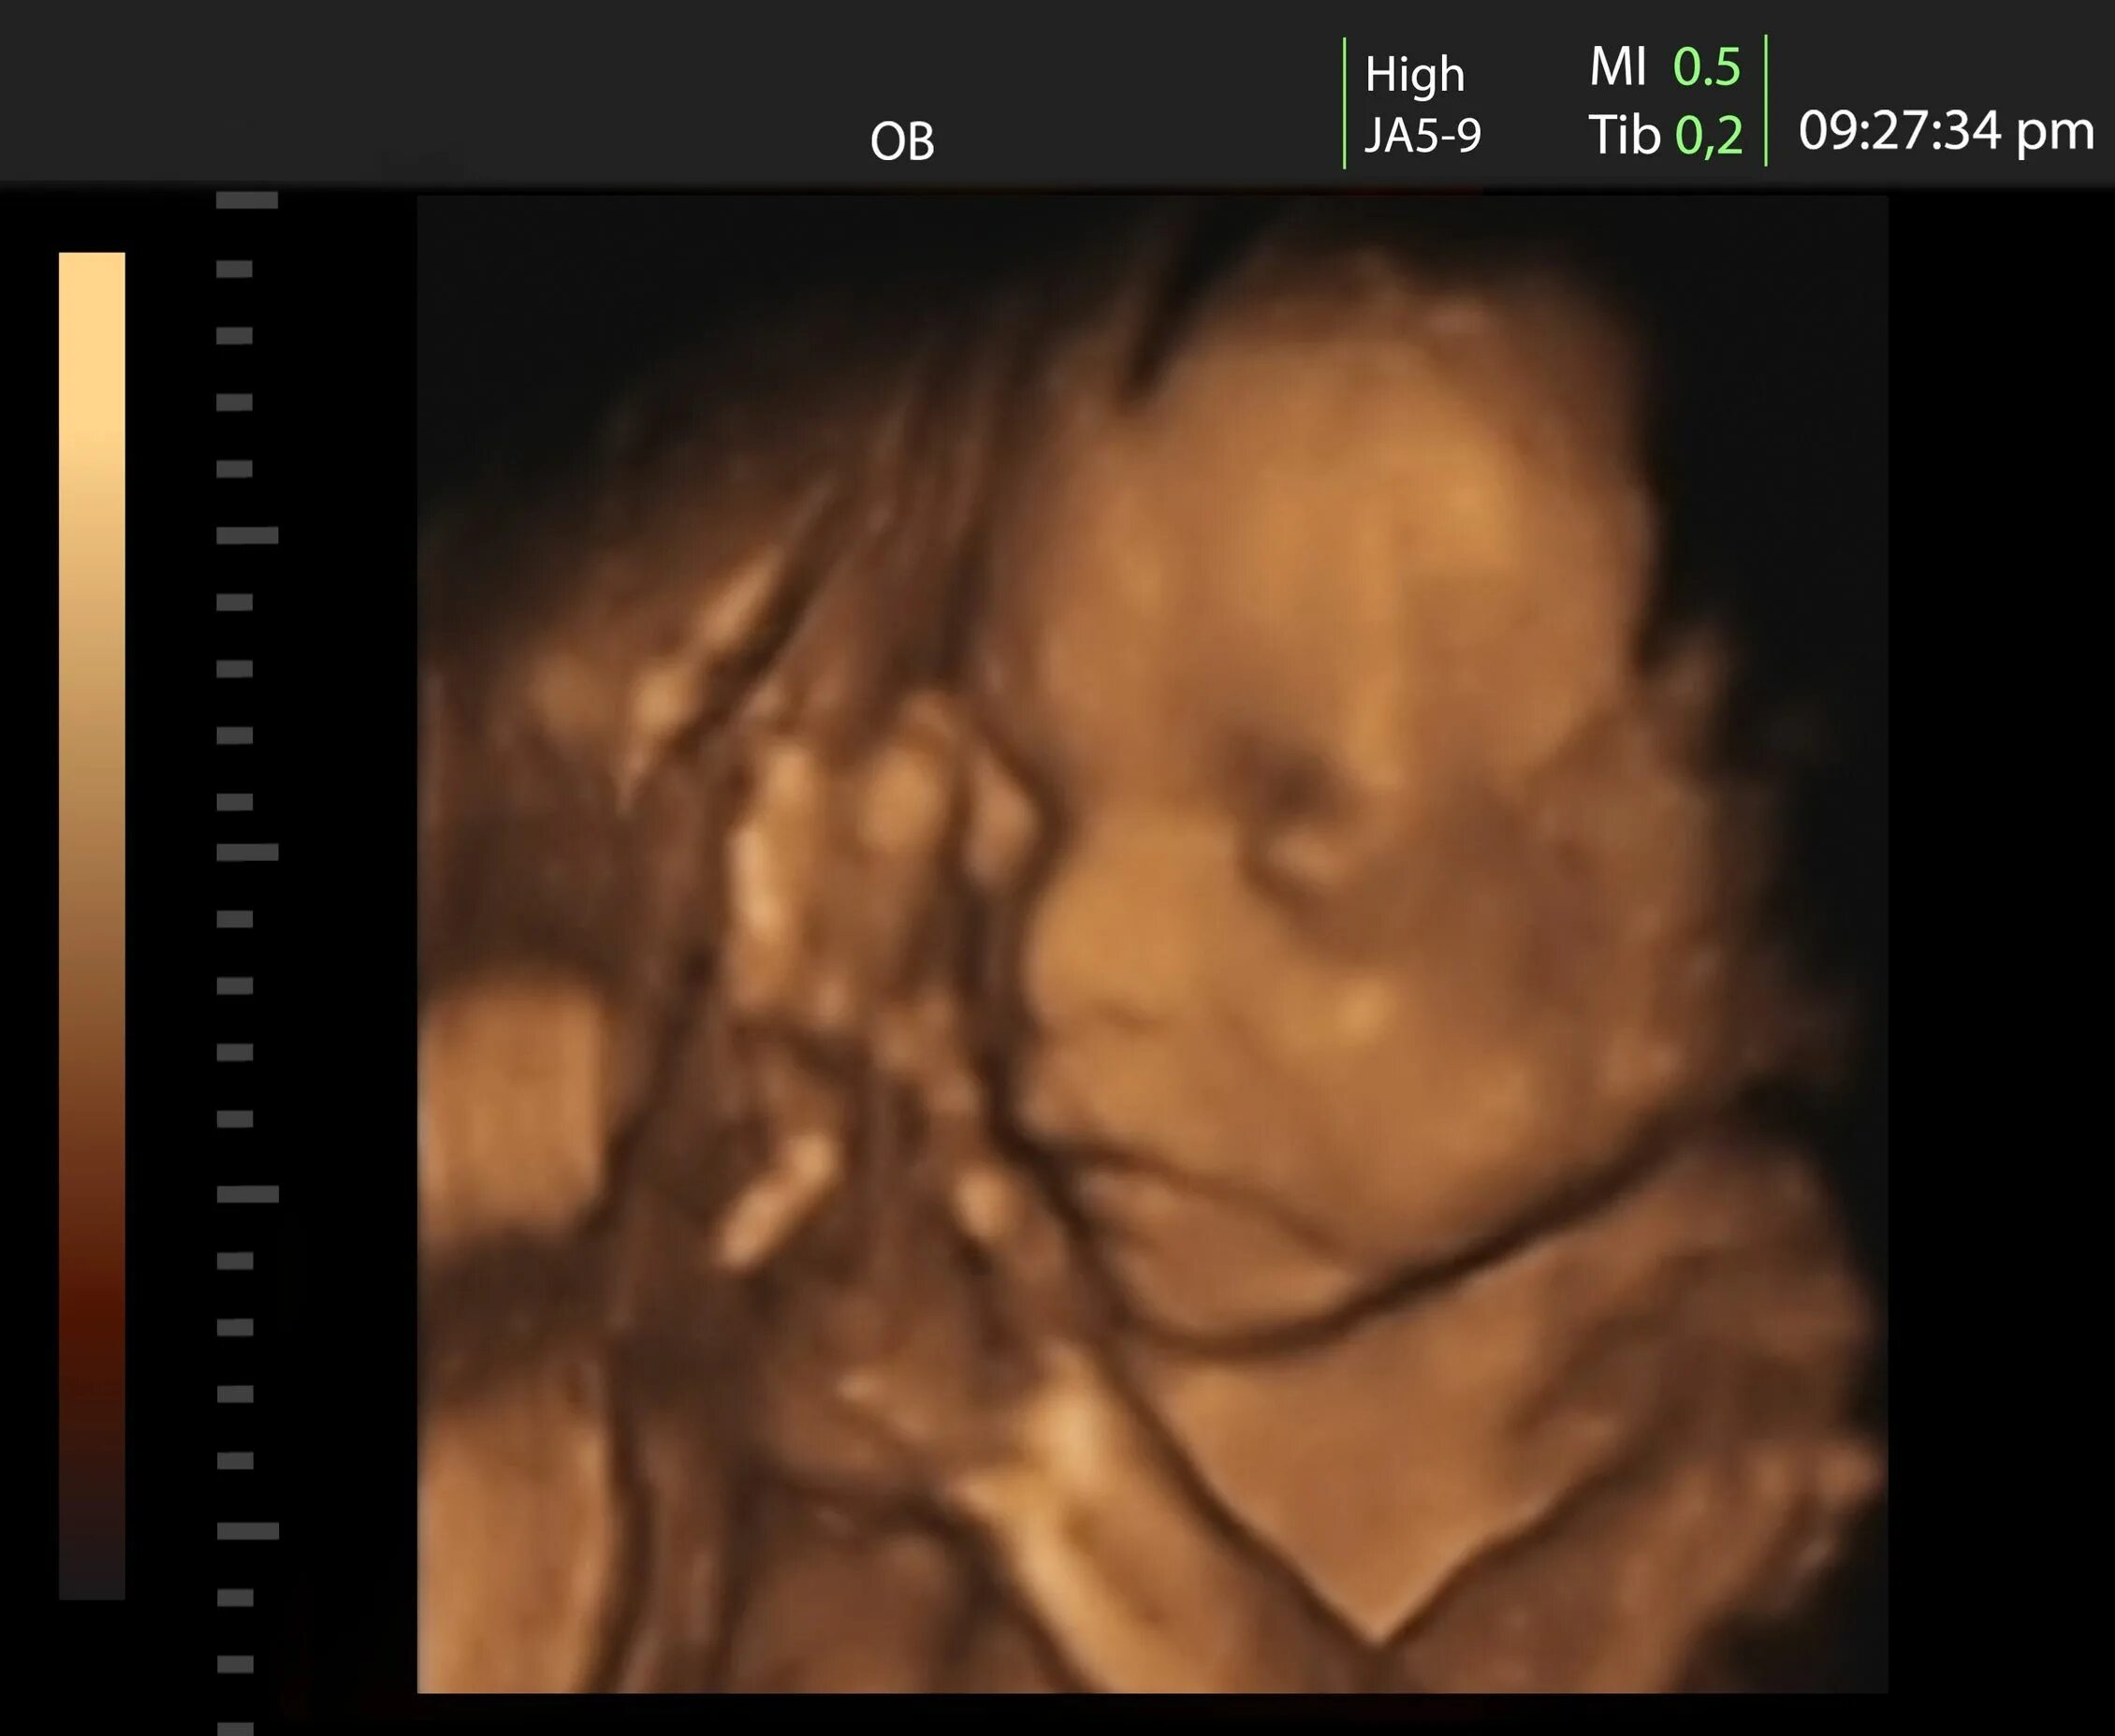

30 неделя 2025